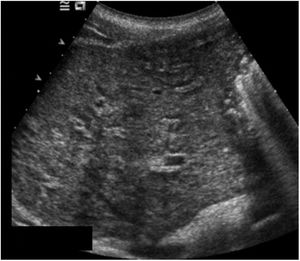

Las exploraciones radiológicas desempeñan un papel importante en el diagnóstico de la enfermedad y sus complicaciones9,29. La radiografía de abdomen puede mostrar principalmente calcificaciones en la pared de la vejiga (fig. 4). La ecografía es la exploración más rentable, permitiendo diagnosticar lesiones en vejiga urinaria como engrosamientos de la mucosa, nódulos (fig. 5), ureterohidronefrosis o la fibrosis periportal (fig. 6) con o sin hipertensión portal característica de la afectación hepatointestinal. Otras exploraciones como la TAC o la RMN pueden ayudar al diagnóstico, sobre todo en casos de localizaciones ectópicas como puede ser el pulmón o el sistema nervioso central. La tabla 2 muestra resumidas las características de las principales pruebas empleadas en el diagnóstico de la esquistosomiasis.